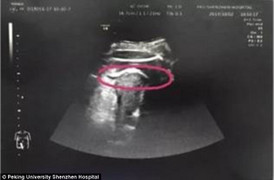

Trước khi được cấy ghép tử cung, cô Davidson và chồng đã thực hiện biện pháp thụ tinh trong ống nghiệm để tạo ra bảy phôi. Những phôi này được đông lạnh để làm thụ tinh trong ống nghiệm tại London.

Sau đó, cô Davidson thực hiện ca phẫu thuật vào tháng 2/2023. Cô được cấy ghép tử cung từ chị gái của mình, Amy Purdie, 42 tuổi, một cựu giáo viên tiểu học, mẹ của hai cô con gái 10 và 6 tuổi. Vài tháng sau, sau khi được ghép tử cung, cô Davidson được chuyển phôi và thụ thai thành công.